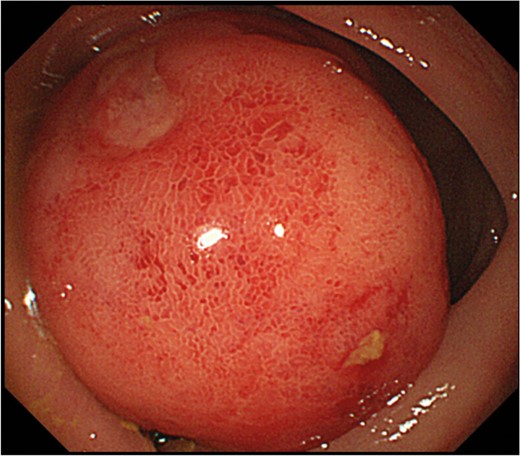

Endoscopic examination showing a pedunculated lesion with the base near the ileocecal valve, occupying most of the transverse colic lumen.